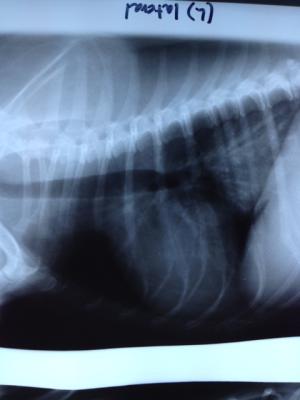

This is a 9 yr old Dachshund who presented to my associate for cough/gagging. Otherwise fine eating , playing etc.  The radiographs showed suspicious mass. The patient was imaged. I am wrestling with the location of this mass? Which side of diaphram? Has anyone  done fna or biopsy here and what is best access point? Which neoplasias have you seen?Thanks

Great post: primary lung

Great post: primary lung mass carcinoma or sarcoma likely, granuloma or fungal in such regions but doubt it. But I have seen cholangiocarcinoma eat right through the liver into the diaphragm like this even though the liver looked ok. i have done fna transdiaphragmatic through the liver with spinal needle or core in a post mortem. I notify onwer/client of risk and do an fna but I am aggressive with needles. Could do CT and exploratory thoracic sx as this is th egold standard for these type lesions.

Another possiblity would be an esophageal mass, with similar causes as mentioned by Eric as well as Spirocerca – could consider doing a scope.